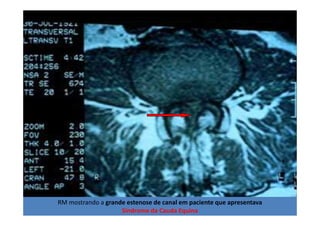

RM - corte sagital de

imagem ponderada em T2

com supressão de gordura

Fonte: Portal da SBC – casos clínicos